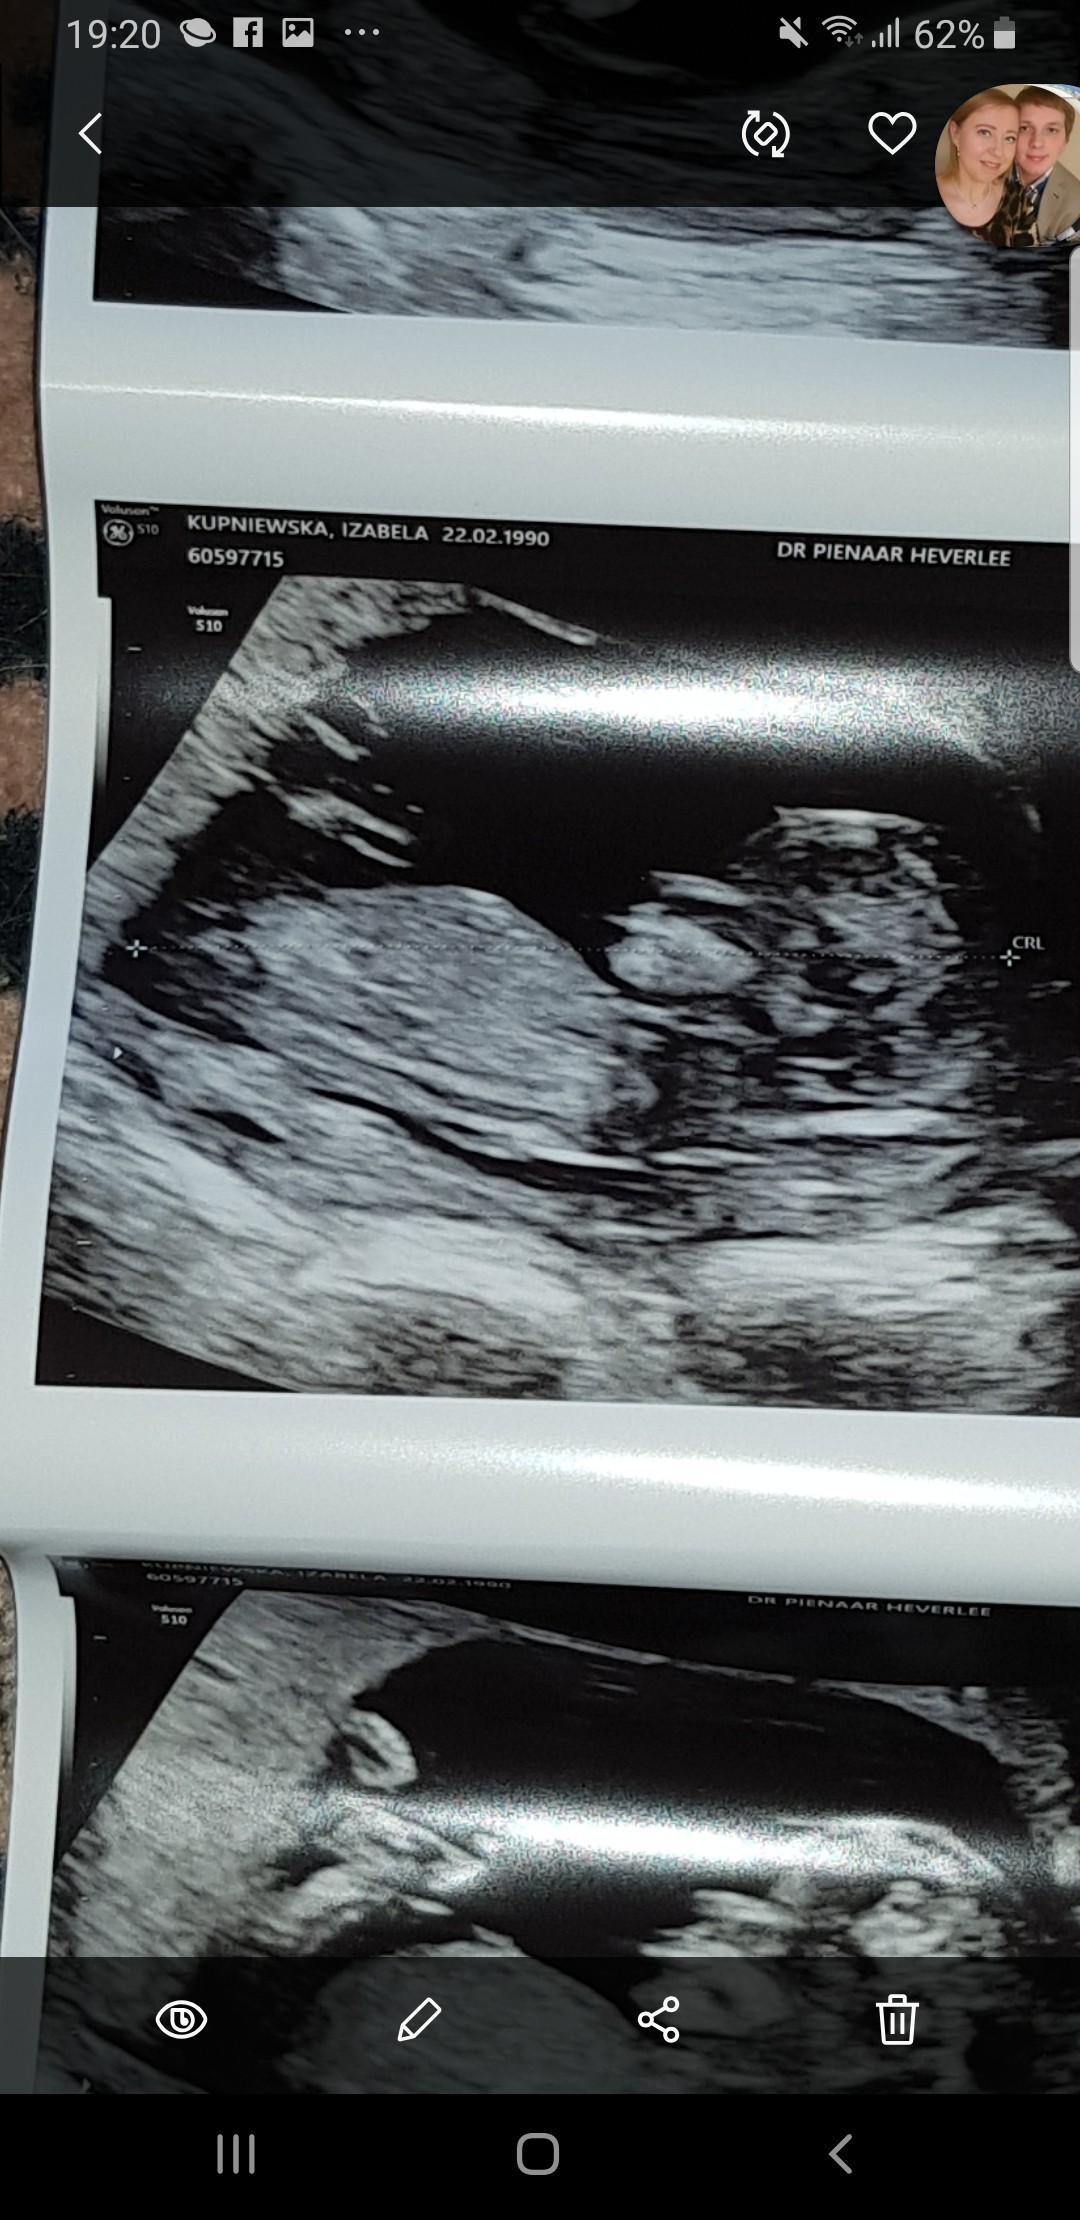

Plec z usg

Zdjecie w zalaczniku. Usg 13sty tydzien. Na moje nie widac tu zadnego wyrostka- jak to mowliwe???Czy w takim razie to dziewczynka? Lekarz sie nic nie chcial wpowiedziec :( Pomozcie dziewczyny specjalistki :*

Na szczescie musze tylko do wtorku czekac na wynik badania NIPT, wiec tylko tydzien od tego usg, ale i tak juz bym chciala wiedziec :P Czas sie jakby zatrzymal ha ha ha Wiem, straszna jestem :-) I jak neta i fora przegladam to juz te wyrostki widac i to nawet dokladnie w takim wieku ciazy.